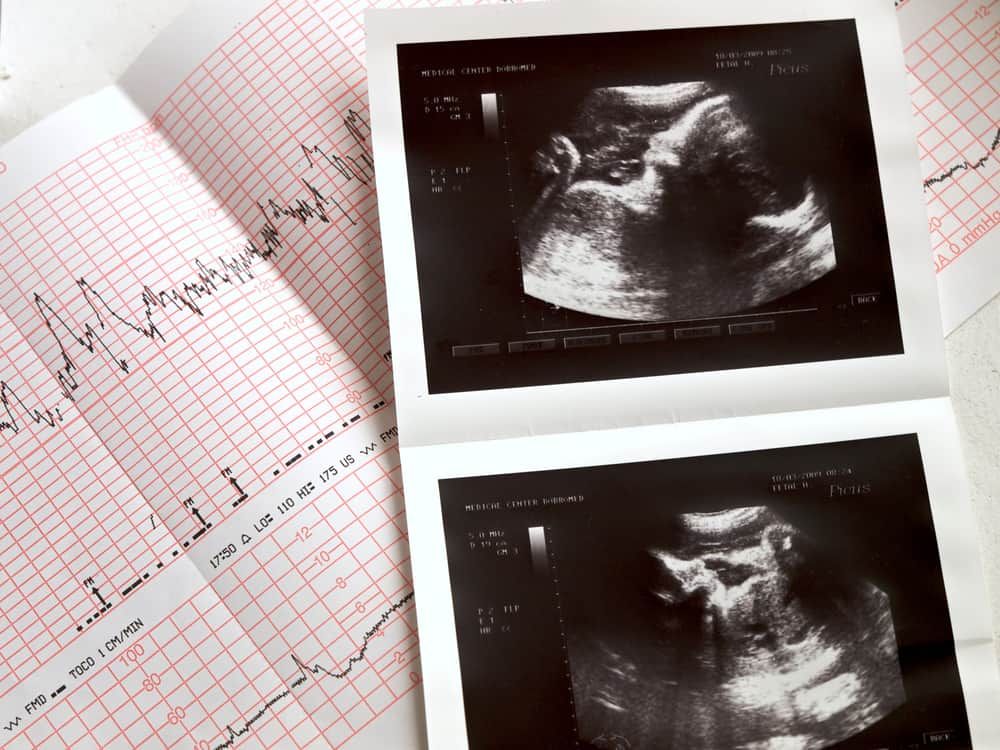

Mỗi bào thai đều trải qua nhiều giai đoạn phát triển và mỗi giai đoạn đều sẽ có những cột mốc đáng nhớ. Lần đầu nghe thấy nhịp tim thai chính là một trong những cột mốc quan trọng đó.

Khi phôi thai ở tuần thứ 5 – 6 của thai kỳ, trái tim sẽ bắt đầu đập khoảng 80 – 85 nhịp mỗi phút, đồng nhất với nhịp tim của mẹ. Trong suốt một tháng đầu tiên, tần suất đập của nhịp tim sẽ tăng lên khoảng 3 nhịp mỗi phút/ngày. Vì thế, việc đếm nhịp tim là cách giúp bác sĩ xác định tuổi thai khi siêu âm.

- Tuần thứ 5: Tim bắt đầu đập và có thể được phát hiện qua siêu âm.